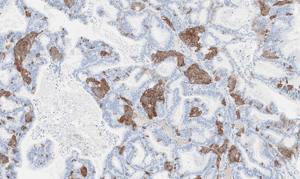

Our screen includes 38 models across head and neck, neuroendocrine, and other clinically relevant tumor types. Each model is annotated with SSTR2 expression data and optimized for radiopharmaceutical evaluation.

Histology

CTG-0258

Ovarian